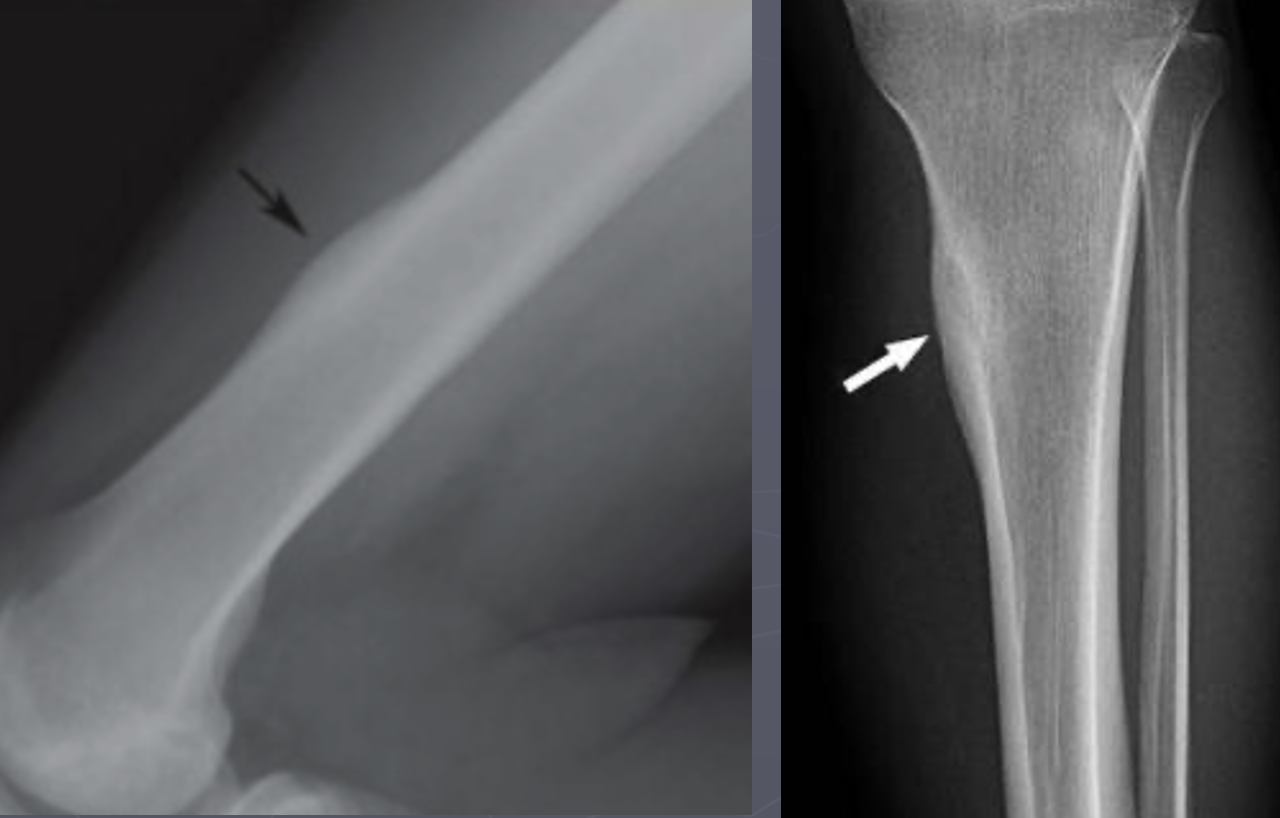

Q

A

Left: immature; more faint

Right: mature; more opaque